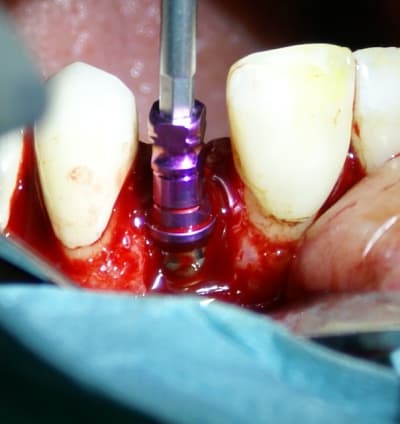

Bien vu! cela demande une petite explication.

j'ai d'abord enfoui le plus apicalement possible ma membrane car je devais en premier lieu combler avec le moignon en place de manière à ne pas mettre de substitut osseux dans l'hexagone interne. Une fois mon substitut en place je travail le porte implant qui sert de support à la provisoire, il y a donc montages et démontages successifs.

Comme tu l'as si bien remarqué, j'ai laissé une minuscule languette de membrane, je l'a tracte très légèrement (une fois seulement la provisoire validée et prête à poser) et la fixe en la transperçant avec le moignon portant la provisoire. ainsi je recouvre bien le substitut osseux en palatin et en vestibulaire également.

remarque:

Cette dernière opération est très délicate quand c'est une vis de cica car elle entraine la membrane en l'enroulant (ce qu'amibien décrit plus haut) .

Suivant les marques d'implants il existe une vis spéciale pour fixer les membranes aux implants.Enfin, je suppose... Chez Xive, cette vis existe mais c'est une vis de couverture et non une vis de cica.